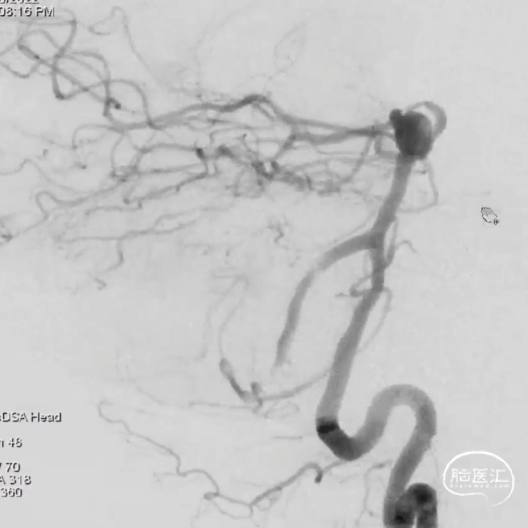

此为左侧大脑中动脉瘤,近端血管极为迂曲,瘤体有突出的子囊,动脉瘤与载瘤动脉有一定夹角,动脉瘤呈上窄下宽形状,M2段下干从瘤颈近端发出。

动脉瘤平均宽度5.41mm, 最小高度为3.71mm,瘤颈约为4.94mm,使用WEB™ SL 6*3mm瘤内扰流装置进行栓塞治疗。

释放WEB™:缓慢推出WEB™从种子至萌芽状态,继续向瘤腔内远端缓慢推送WEB™至萌芽至开花间状态;将WEB™和VIA™送至瘤顶,固定WEB™推送杆回撤VIA™,WEB™完全释放。

经造影可见WEB™尺寸合适,贴合瘤壁,覆盖瘤颈,且下支M2段分支及其他分支血管血流通畅。

解脱后,再次造影和Dyna-CT评估,可见动脉瘤瘤腔内有明显造影剂滞留,分支血管血流正常。